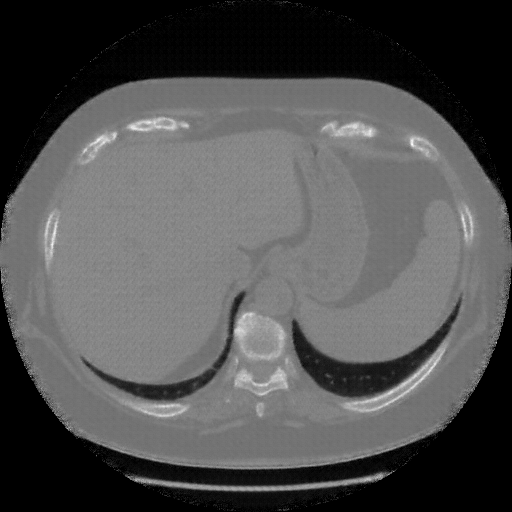

Reconstructed NATIVE CT scan (cycle consistency)

Full window (WL 1023.5, WW 4095 β†’ Low βˆ’1024, High +3071)

Actual HU range: [-1024.0, 1214.3]

Lung window (WL -600, WW 1500 β†’ Low βˆ’1350, High +150)

Actual HU range: [-1350.0, 150.0]